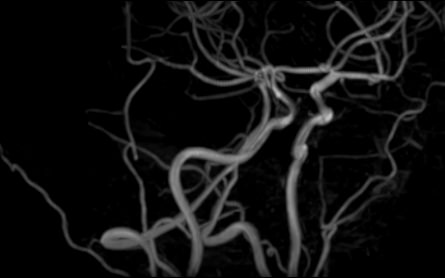

Стандартная МРТ головного мозга дает важную информацию о состоянии и структуре мозговой ткани для выявления большого числа заболеваний, в том числе опухолевых образований, демиелинизирующих заболеваний, воспалительных процессов головного мозга и мозговых оболочек. Стандартную МРТ головного мозга дополняет МР-ангиография, которая отображает состояние системы кровоснабжения головы и шеи. Компьютерная программа обрабатывает данные, полученные при сканировании, и формирует объемные изображения как самого мозга, так и сосудистой системы в отдельности без прилегающих тканей. Обе методики применяются одновременно и взаимодополняют друг друга, давая полную диагностическую картину.

Исследование предоставляет информацию о состоянии тканей головного мозга и оболочек, проходимости кровеносных сосудов, наличии и размерах опухолей, тромбов, гематом и других патологий. Изучив изображения, нейрохирург или другой специалист получает информацию о локализации патологии, степени повреждения тканей мозга, может принять решение о проведении операции либо контролировать ход лечения.